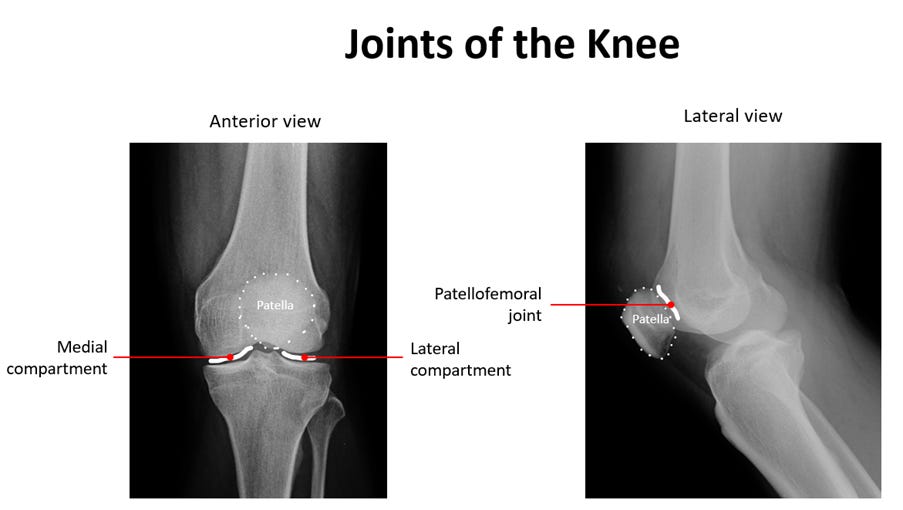

Knee osteoarthritis is a common cause of pain, stiffness, and reduced mobility, especially with age. Symptoms often develop gradually and may include pain during movement, …